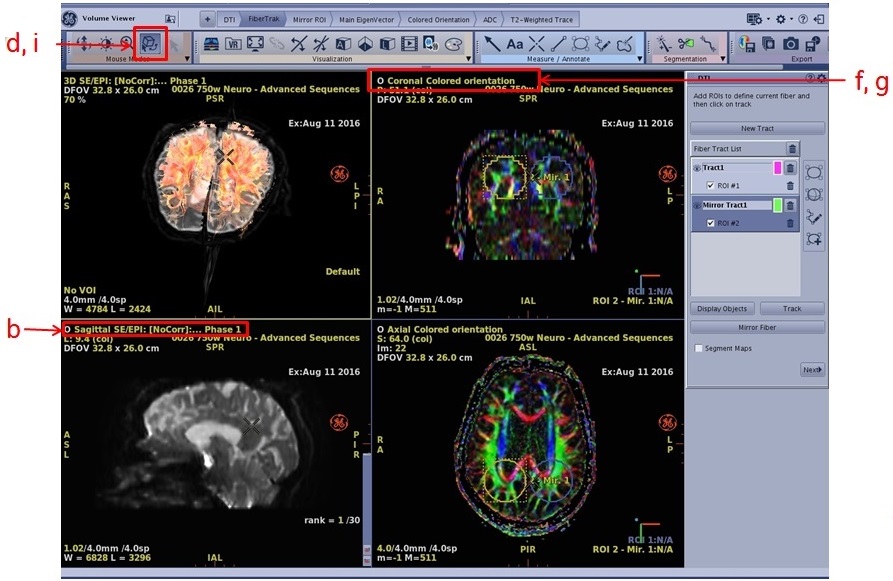

- To create the DTI FiberTrak view, follow these steps.

- From the DTI FiberTrak screen, click New Tract.

- Click one of the ROI icons from the DTI FiberTrak screen.

- Position the cursor over the area of interest and click to deposit the ROI. Size and shape the ROI as needed.

- Click Track to generate updated tracking fibers.

- Each time you add a new tract, the system automatically assigns a tract color. To change the color of the tract:

- Click the color icon next to the trash can and a color palette appears.

- Click and drag the color cursor over the desired color.

- Click the X on the color palette window to close it.

- To apply color scheme to the fiber tracts, place the cursor in the fiber tract viewport and right-click on the yellow Default and then click User Color.

- Repeat these steps for the additional FiberTraks

Figure 4. Create FiberTrak